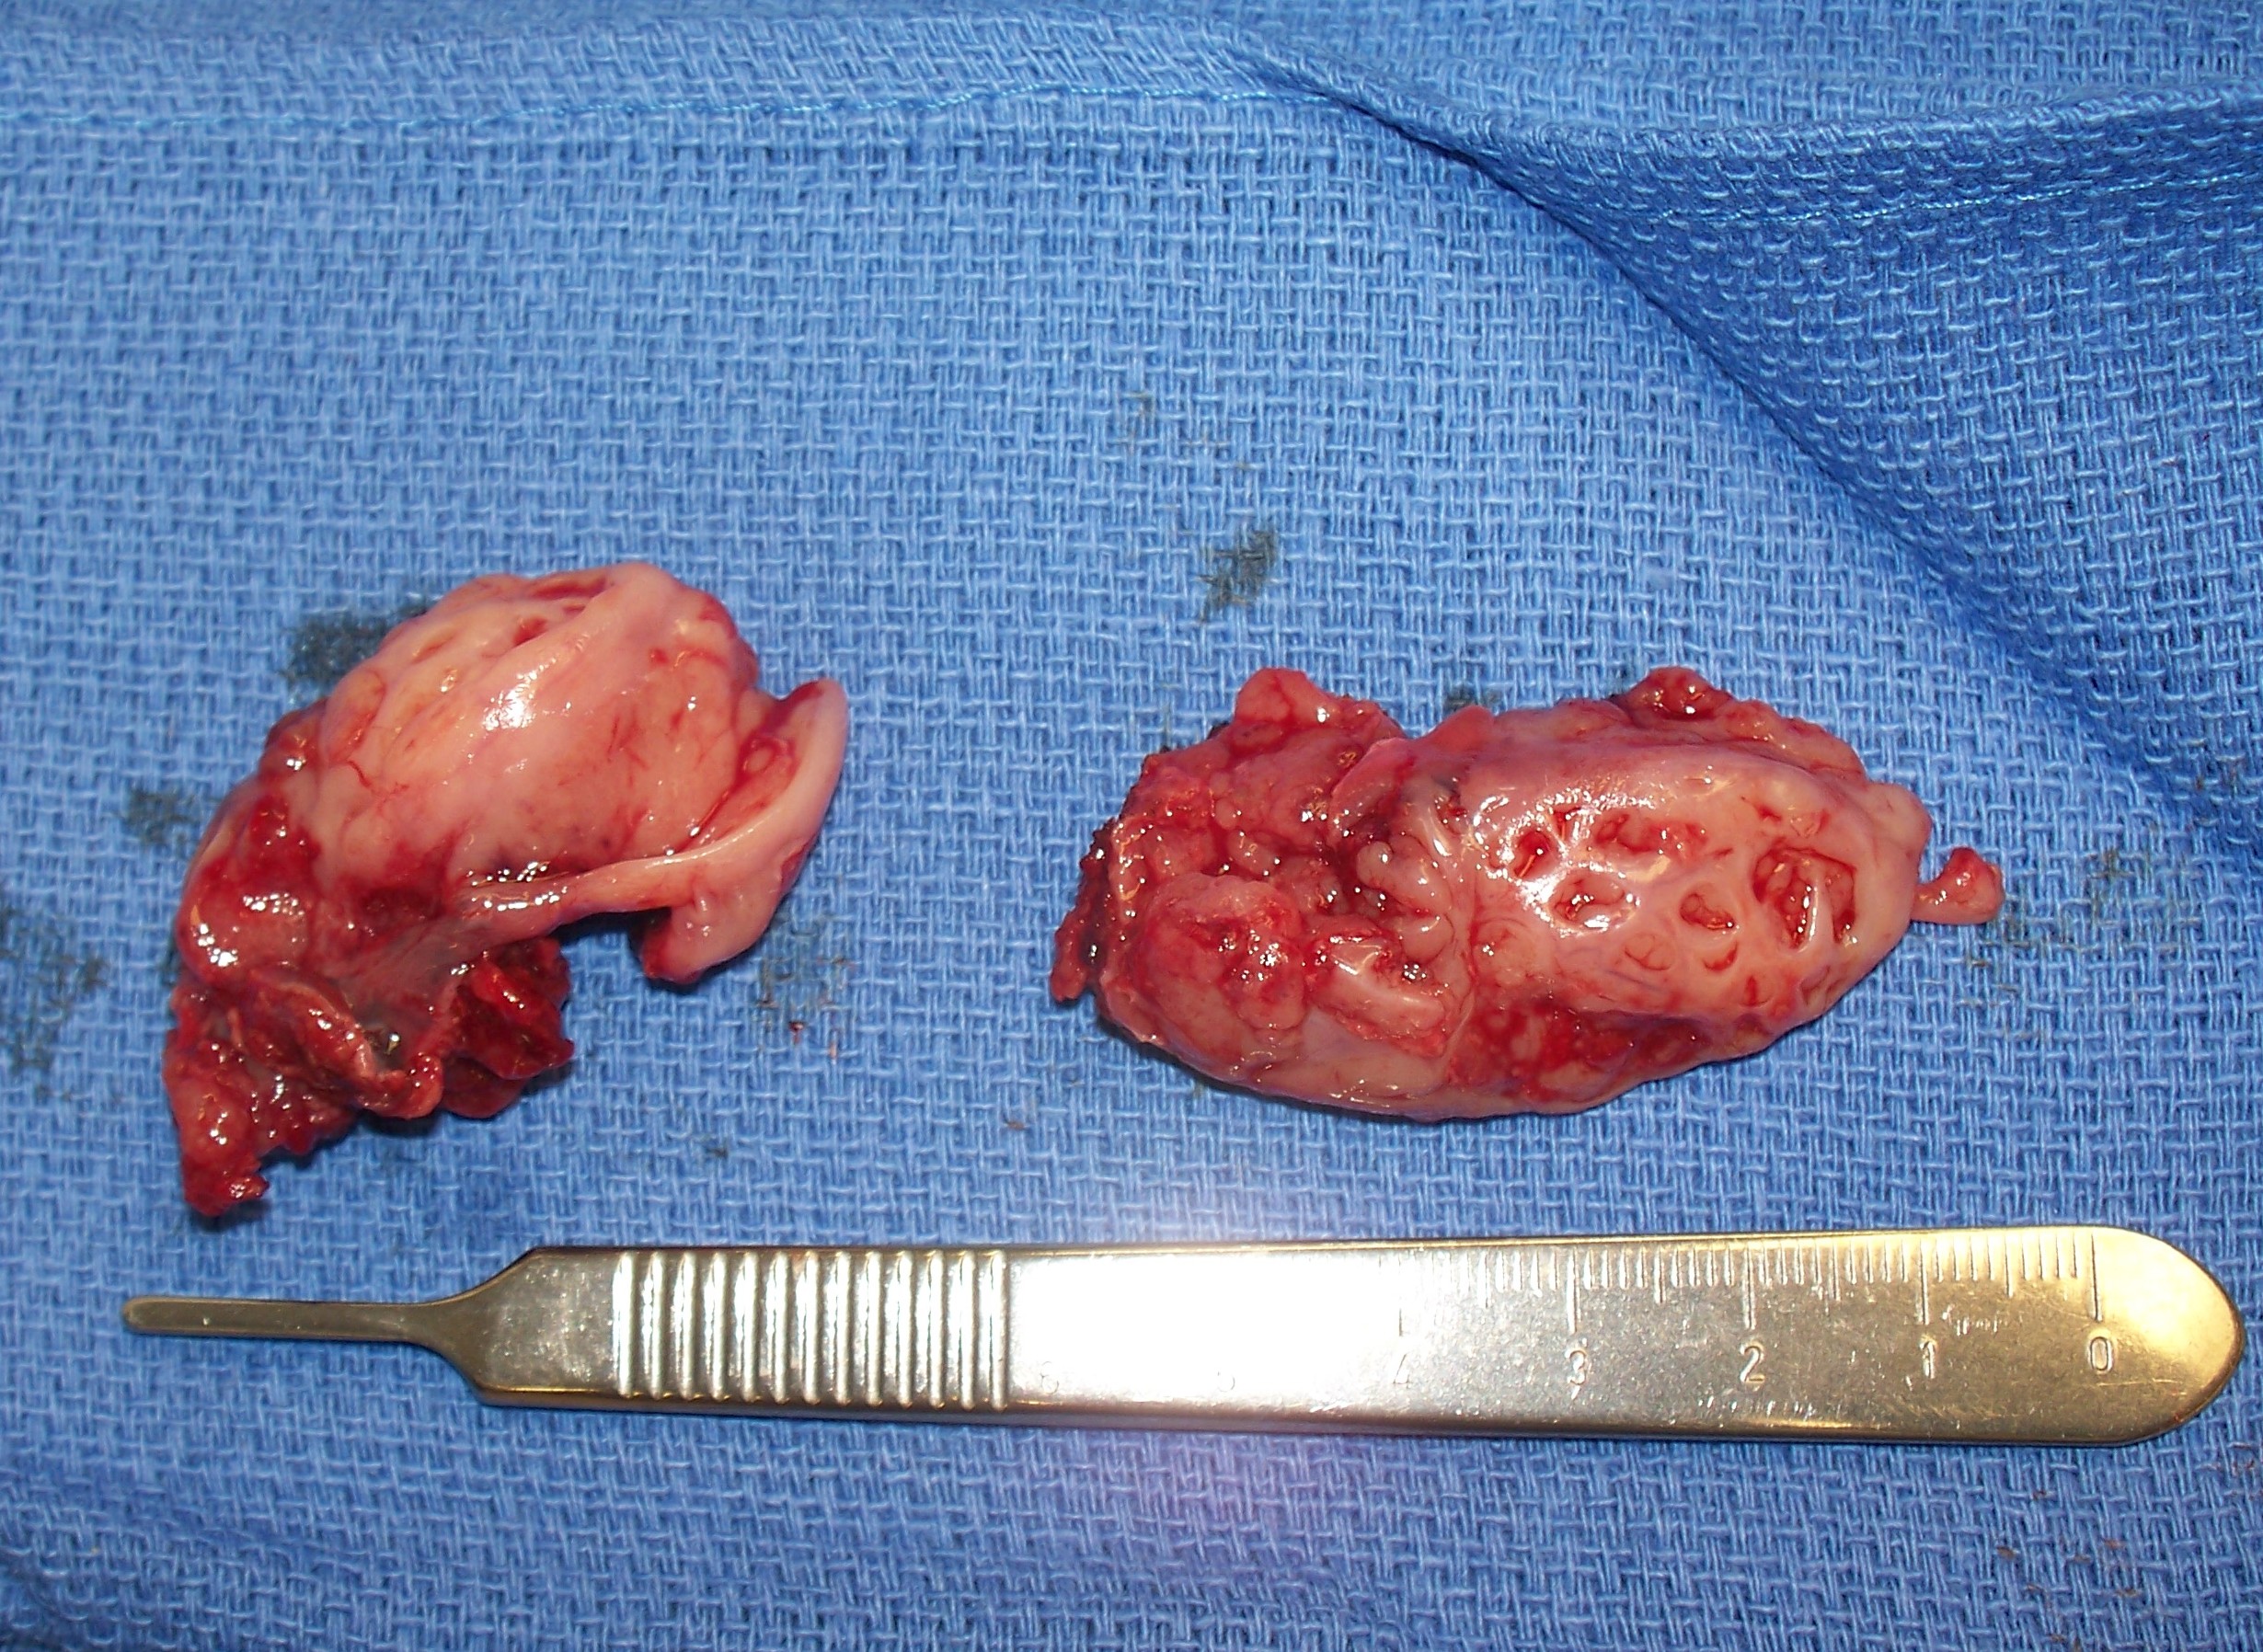

편도절제술은 편도염이나 수면 무호흡증 치료를 위해 시행되는 수술이다. 의학적 용도로는 편도 주위 농양, PFAPA 증후군, 코 기도 폐쇄, 편도암, 디프테리아 보균 상태 등이 있으며, 소아의 경우 아데노이드 제거술과 함께 시행되기도 한다. 잦은 인후통, 즉 편도염의 경우, 지난 1년 동안 7번 이상, 지난 2년 동안 매년 5번 이상, 또는 3년 동안 매년 3번 이상의 인후 감염이 있는 경우에 권장된다. 수술 방법으로는 메스, 전기 소작, 고주파 열 절제, 코블레이션, 하모닉 메스, 열 용접, 이산화탄소 레이저, 미세 절제기 등이 사용된다. 수술 후에는 인후통, 출혈, 탈수 등의 합병증이 발생할 수 있으며, 회복 기간 동안 적절한 수분 섭취가 중요하다.

편도절제술은 다양한 방법으로 시행될 수 있다. 지난 50년간은 주변 근막에서 편도선을 절개하는 완전 절제술이 주로 시행되었으나, 최근에는 합병증을 줄이기 위해 부분 편도 절제술(편도 절개술)에 대한 관심이 높아지고 있다.[33]

4. 1. 절제 및 올가미 방법

이비인후과 의사가 과거에 가장 흔하게 사용했던 방법은 겸자와 가위, 그리고 올가미라고 하는 철사 루프를 사용하여 편도를 제거하는 것이었다.[34] 이 절차는 환자가 전신 마취를 받아야 하며, 편도는 완전히 제거되고 남은 조직 표면은 소작한다. 환자는 수술 후 출혈이 최소화된 상태로 퇴원한다. 하지만 다른 기술들이 선호되면서 이 방법은 점차 사용되지 않게 되었다.4. 2. 전기 소작